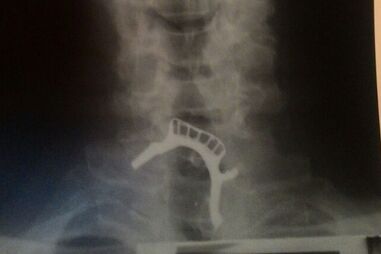

Hospital não dispunha de aparelho de endoscopia para retirar o objeto de dentro do paciente.